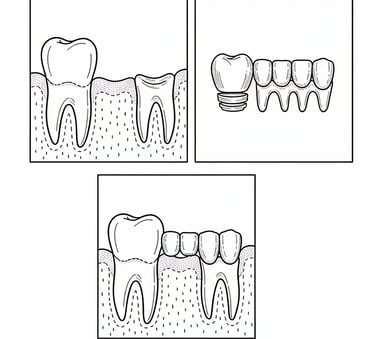

Προσθετική εργασία

Ψηφιακή ακτινογραφία

Η προσθετική εργασία περιλαμβάνει αποσπώμενες οδοντικές αποκαταστάσεις που αντικαθιστούν τα χαμένα δόντια και το μαλακό ιστό. Προσφέρει βελτίωση στην αισθητική, την ομιλία και τη μάσηση, είναι οικονομικότερη και εύκολη στην επισκευή.